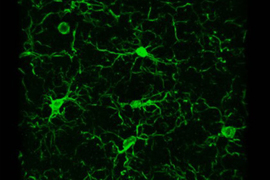

To confirm the significance of that finding, the researchers directly examined the hippocampus in stimulated and control mice. They found that in a critical subregion, the dentate gyrus, stimulated mice had significantly more synapses.

The team’s analysis of genetic data suggested that TCF4 is underexpressed in Down syndrome mice, but the researchers saw improved TCF4 expression in GENUS-stimulated mice. When the researchers went to the lab bench to determine whether the mice also exhibited a difference in neurogenesis, they found direct evidence that stimulated mice exhibited more than unstimulated mice in the dentate gyrus. These increases in TCF4 expression and neurogenesis are only correlational, the researchers noted, but they hypothesize that the increase in new neurons likely helps explain at least some of the increase in new synapses and improved short-term memory function.

This study is the first to document that GENUS is associated with increased neurogenesis.